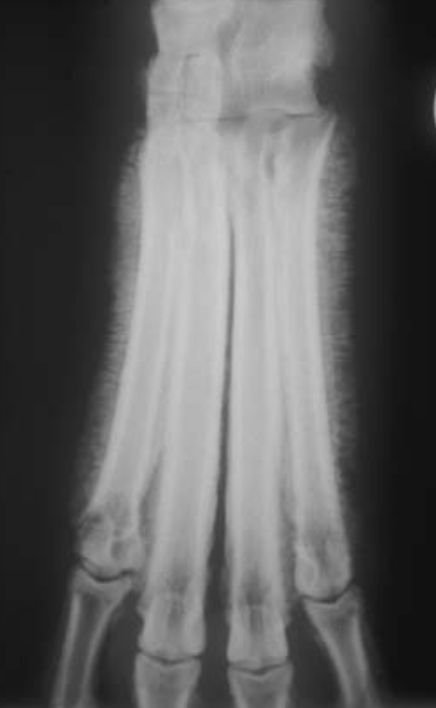

Thin brush-like

periosteal reaction of the abaxial

surface of metatarsals II andVinacaseof hypertrophic osteopathy.

A

Thick brush-like

periosteal reaction on the abaxial

surface of metacarpal V in a dog with hypertrophic osteopathy.